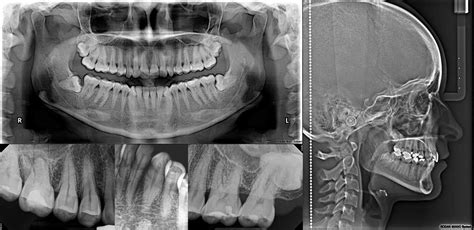

Ejemplo de radiografía dental digital.

Existen diversos tipos de radiografías, cada una diseñada para una necesidad específica:

- Radiografía periapical: Centrada en un diente en particular.

- Radiografía panorámica: Abarca toda la boca, proporcionando una visión integral de la cavidad bucal.